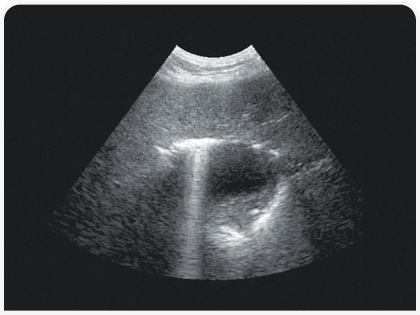

Рентгенография позволяет определить размеры, форму, положение, непрозрачность и края печени, а также обнаружить скопления газа или минерализацию (Рисунок 2). Ультразвуковое исследование помогает определить распространенность поражения печени (очаговое, многоочаговое или диффузное), а также оценить степень васкуляризации и облегчить получение образцов (для цитологического и культурального исследований и биопсии) (Рисунок 3). Однако следует помнить, что отсутствие патологических изменений при ультразвуковом исследовании не всегда свидетельствует о здоровье печени.

Цитологическое исследование ткани печени особенно важно при наличии многоочаговых или диффузных метаболических или опухолевых поражений (например, при круглоклеточной опухоли, вакуолярных гепатопатиях) (Рисунок 4). Его чувствительность по сравнению с гистопатологическим исследованием низкая; тем не менее этот метод диагностики быстрый, минимально инвазивный и безопасный, поэтому я во многих случаях рекомендую применять его в качестве первого инвазивного исследования ткани печени. Еще один полезный минимально инвазивный метод, редко сопровождающийся осложнениями, – холецистоцентез под контролем ультразвукового исследования (14).